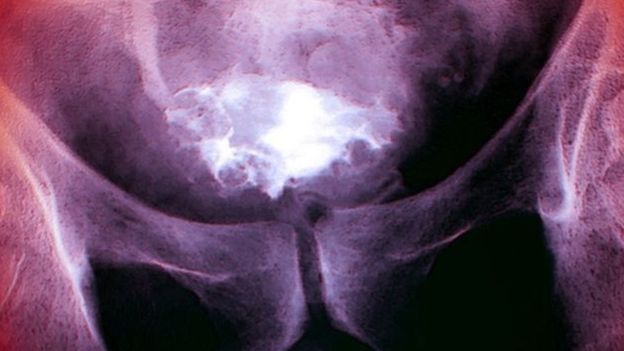

وهذا النوع من سرطان المثانة، الذي يتكون في مجرى البول ولا تغزو خلاياه المثانة من الخارج، يأتي في المرتبة العاشرة بين أكثر أنواع السرطان انتشارا في بريطانيا. ويصيب حوالي 10 آلاف حالة جديدة كل عام.

أجريت هذه الدراسة على 15 مريضا بسرطان المثانة، تم حقنهم بفيروس كوكساكي القاتل للسرطان (CVA21) باستخدام قسطرة، قبل أسبوع واحد من جراحة لإزالة الأورام.